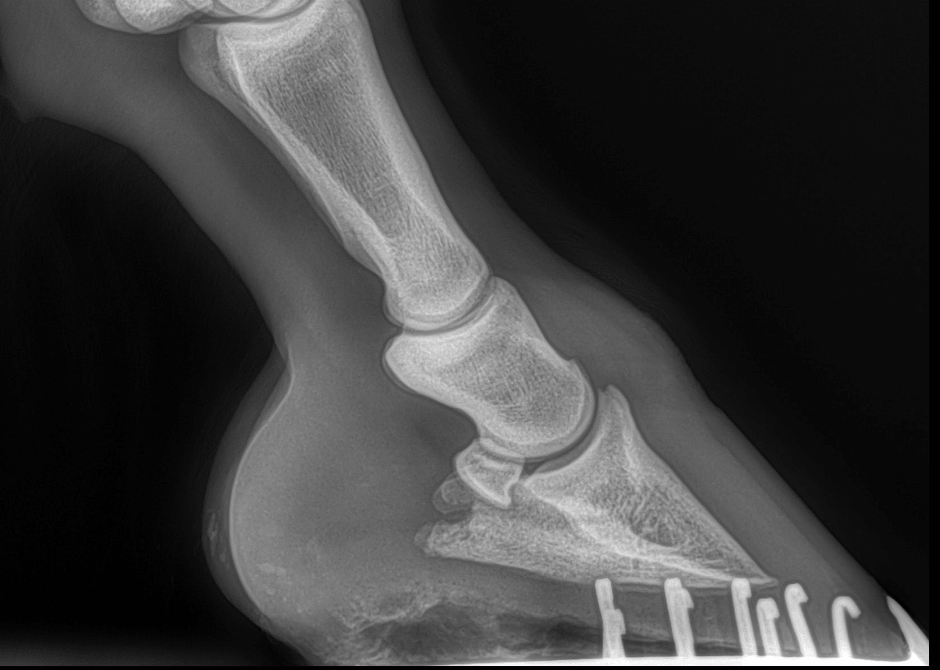

- Eine Röntgenaufnahme: Unverzichtbares Hilfsmittel zur Identifizierung der WLD

Eine Röntgenaufnahme stellt in bestimmten Fällen ein interessantes Hilfsmittel bei der Erkennung und Diagnose der Erkrankung der weißen Linie im Pferdehuf dar, da sie detaillierte Informationen über die inneren Strukturen liefern kann.

Darstellung von Knochenstrukturen :

Röntgenaufnahmen ermöglichen eine genaue Darstellung der knöchernen Strukturen des Hufes, einschließlich der Wand, der Sohle und des Strahls. Betroffene Bereiche können auf dem Röntgenbild als verschwommene oder verblasste Bereiche erscheinen.

Erkennung abnormaler Bereiche :

Indem sich die WLD in den Huf gräbt, entstehen Bereiche und Hohlräume, die visuell schwer zu erkennen sind. Mithilfe von Röntgenaufnahmen können diese abnormalen Bereiche entdeckt werden, die auf das Vorhandensein einer Erkrankung der weißen Linie hinweisen könnten, selbst in einem frühen Stadium, in dem äußere Anzeichen noch fehlen.

Die Beurteilung von Stützstrukturen :

Das Röntgenbild hilft bei der Beurteilung der Beschaffenheit der Stützstrukturen des Hufes, wie z. B. der Hornschicht und der Anatomie des Hufes.

Überwachung der Fortschritte :

Röntgenaufnahmen bieten auch eine effektive Möglichkeit, die Entwicklung der Krankheit der weißen Linie im Laufe der Zeit zu verfolgen. Dadurch können Pferdemediziner die Wirksamkeit der angewandten Behandlungen bewerten und die Interventionen entsprechend anpassen.